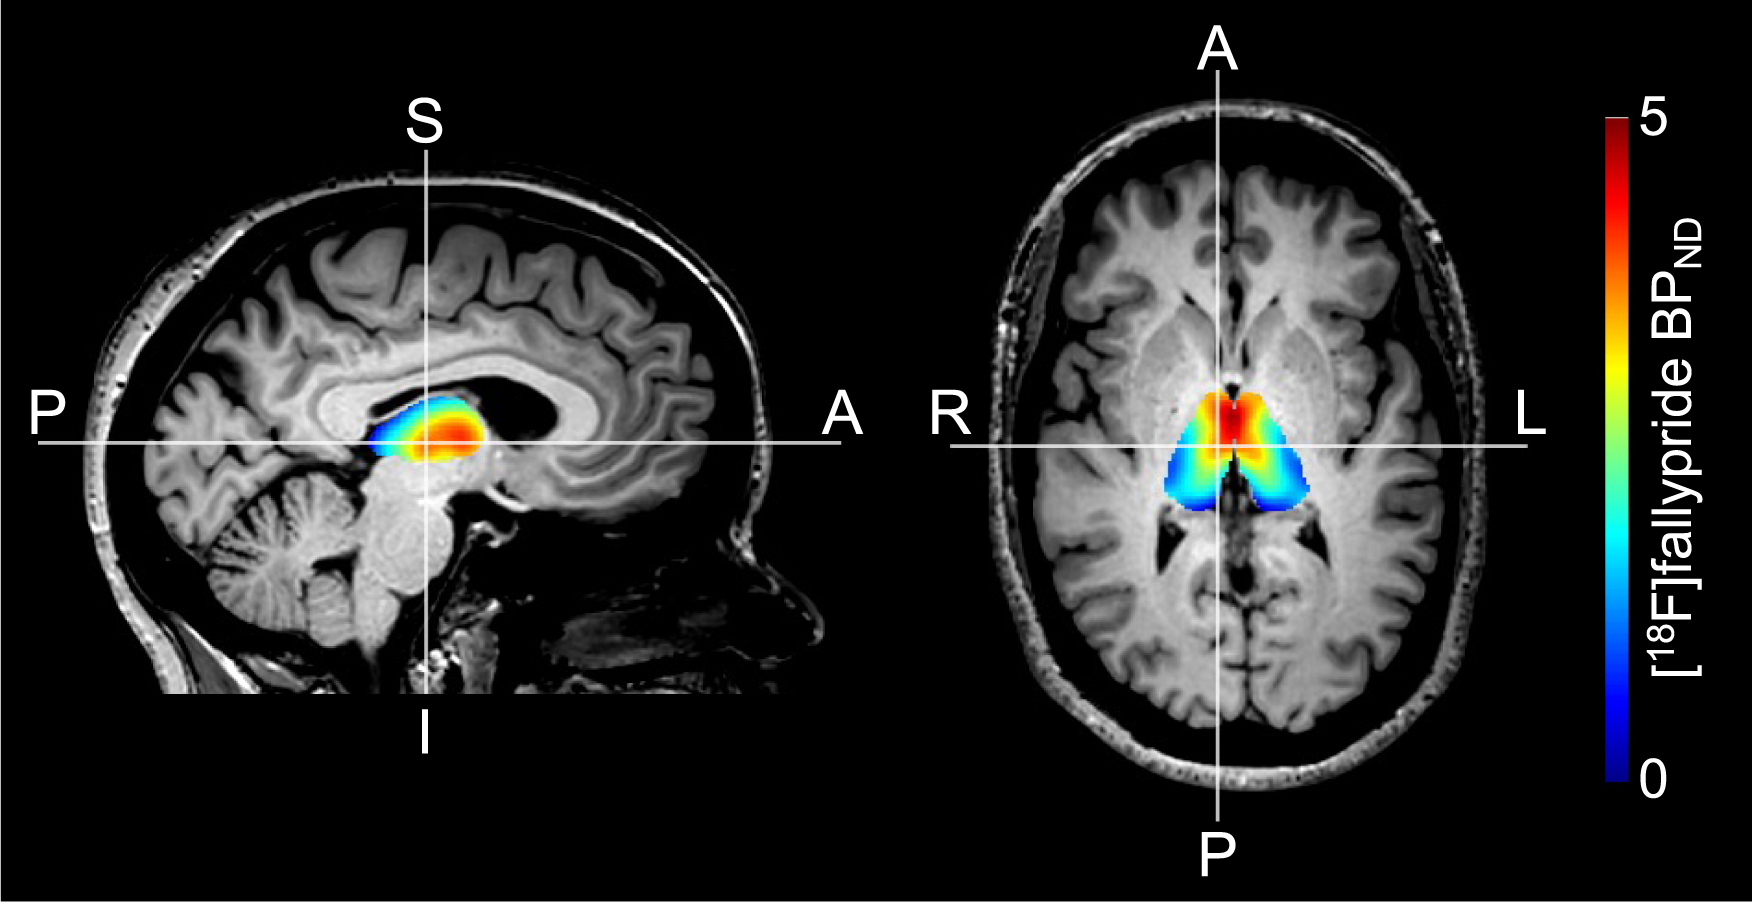

Fig. 3: Thalamic [18F]fallypride BPND.

Representative example of [18F]fallypride BPND values in the thalamus overlaid on a T1-weighted image.